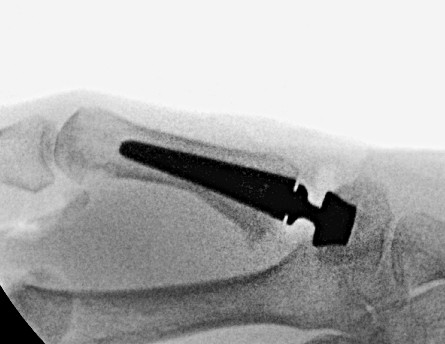

Radiografie na het plaatsen van een duimbasisprothese

Illustratie van duimbasisprothese